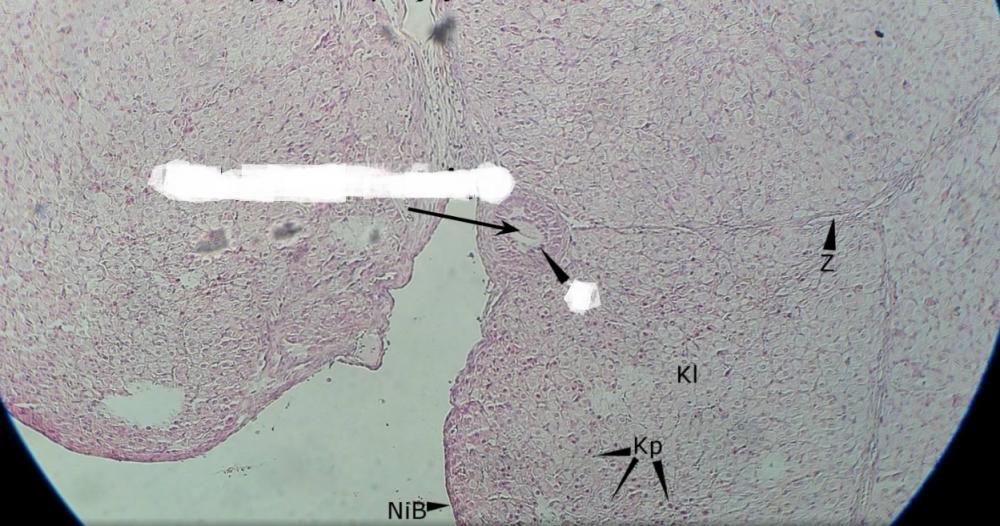

Pytanie 489

ciałko żółte (jajnik, ciałko żółte)

Pytanie 490

ciałka żółte (jajnik, ciałko żółte)

Pytanie 491

tkanka łączna (jajnik, ciałko żółte)

Pytanie 492

pęcherzyk wzrastający (jajnik, ciałko żółte)

Pytanie 493

komórki paraluteinowe - ciemne, wyróżniające się wśród jasnych (jajnik, ciałko żółte)

Pytanie 494

komórki luteinowe - jasne, jest ich bardzo dużo (jajnik, ciałko żółte)